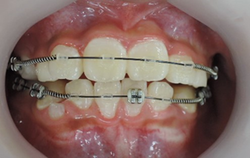

上顎から矯正装置を装着していきます。

上顎の歯が揃ってから、下額に矯正装置(ブラケット)を装着します。